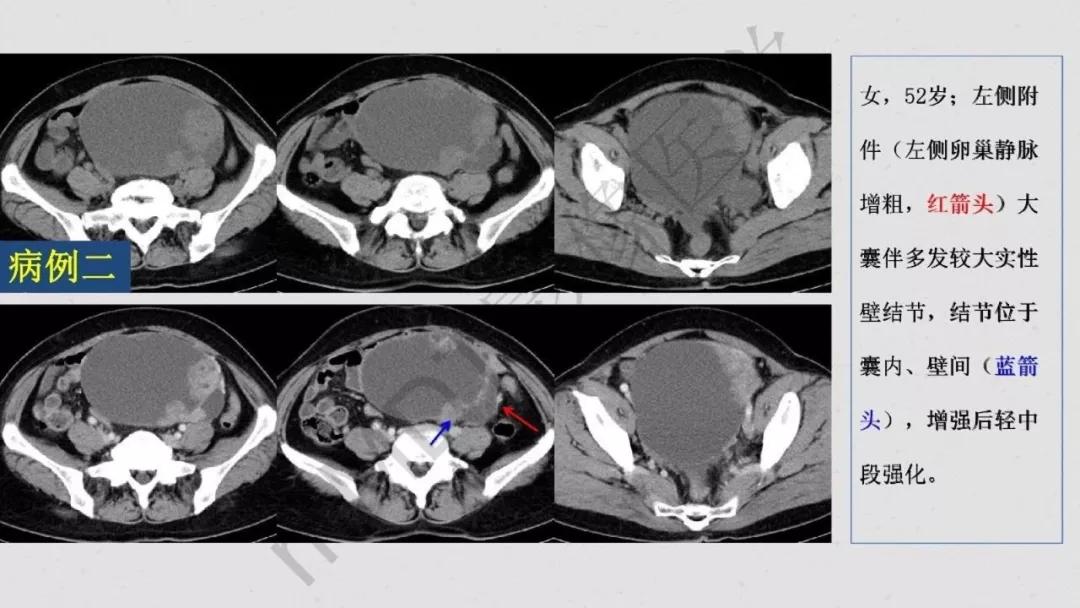

出现钙化:浆液性肿瘤、卵泡膜纤维瘤、畸胎瘤、Brenner瘤